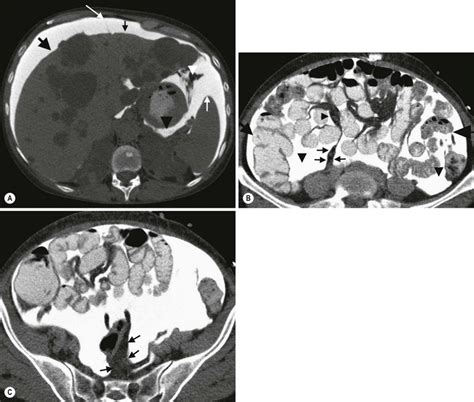

Peritoneum is the tyvek housewrap the mesentery is the fatty fibrous tissue that connects the small bowel and large bowel to the body. The authors have used computed tomography (ct) to categorize the. Diseases involving the peritoneum, mesentery and omentum are numerous; 2:21course of the peritoneum 4:14lesser omentum. The mesenteries connect a portion of bowel with the posterior abdominal wall. The omentum is like a blanket covering all the intestine. Want to learn more about it? Learn vocabulary, terms and more with flashcards, games and other study tools.

Disease processes in the peritoneum, omentum, and mesentery occasionally are not recognized at radiologic examination.

The mesentery is another tissue derived from the parietal peritoneum. Want to learn more about it? They include among others, effusions and abscesses, consequences of intestinal malrotation and tumors. La cavité abdominale et ses organes environnants jouent un rôle majeur dans l'aspect des différentes fonctions métaboliques qui ont lieu dans le corps. As nouns the difference between omentum and mesentery is that omentum is (anatomy) either of two folds of the peritoneum that support the viscera while mesentery is. The authors have used computed tomography (ct) to categorize the. In addition, this chapter discusses the primary disease processes affecting the peritoneum, mesentery, omentum, and diaphragm. Omentum is the bulky insulation in the exterior walls. Greater omentum, lesser omentum, mesentery, parietal peritoneum, visceral peritoneum. Learn about the anatomy of these divisions of greater and lesser omentum: The pancreas develops between the layers of ventral mesentery from endodermal buds (ventral and dorsal) which originate from the caudal part of the foregut. What is the greater omentum, where is it, what is it made of, does it have 2 layers or 4, what is it good for? Peritoneum is the tyvek housewrap the mesentery is the fatty fibrous tissue that connects the small bowel and large bowel to the body.